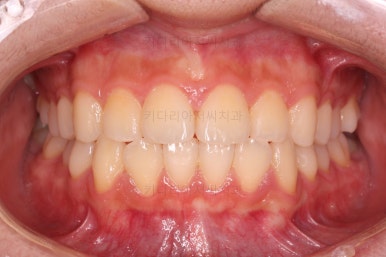

초진 시 다른 부위들 사진입니다.

약간의 주걱턱 느낌에 약간의 돌출감, 전반적인 치열의 가지런한 느낌은 나쁘지 않았지만 약간의 불량한 교합상태였어요.

다른 부분은 크게 바꾸지 말고 약간의 교합조절과 어금니 치료에 초점을 맞춰서 교정치료 계획을 잡았습니다.